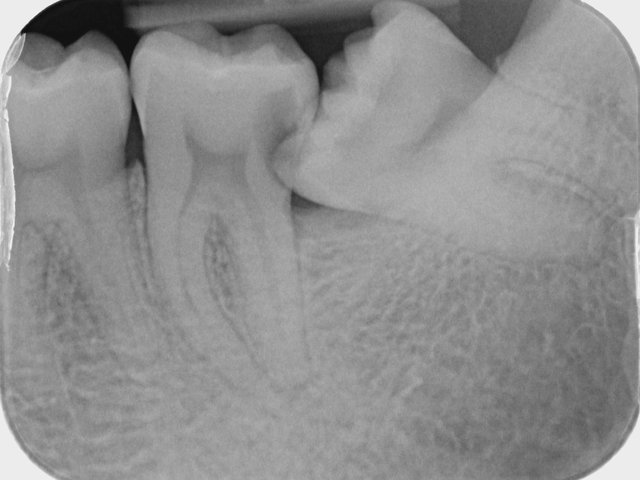

Verlagerung und Retention

Tiefe Karies wegen eines benachbarten Weisheitszahnes

Tiefe Karies wegen eines benachbarten Weisheitszahnes ...